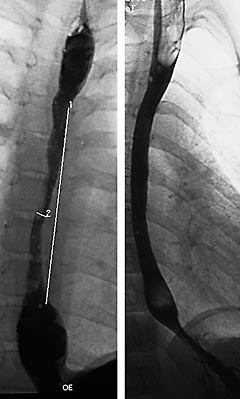

Pasient 1 . Ni år gammel jente som på grunn av gastroøsofageal refluks ble behandlet med cisaprid fra sju måneders til to års alder. I de følgende årene var hun ikke plaget av brekninger, men hun hadde tidlig metthetsfølelse og vansker med å svelge. På grunn av svelgevanskene ble det ved åtte års alder utført en røntgenundersøkelse av øvre gastrointestinaltractus som viste en langstrakt oesophagusstriktur (fig 1a). Vekt i forhold til høyde var ved 10. percentil. 24-timers pH-registrering viste økt refluksindeks (15,8 %), hvor lengste refluksepisode varte 52 minutter. Ved oesophagusmanometri var det ikke normale, propulsive trykkbølger, men simultan trykkstigning i alle oesophagusprobene. Funnet er forenlig med manglende normal peristaltisk bevegelse i oesophagus. Det lyktes ikke å lokalisere nedre sfinkter. Strikturen ble endoskopisk verifisert. Hun ble behandlet med cisaprid, omeprazol og endoskopisk blokking. Det var lite besvær allerede etter fire blokkinger, og ny røntgenundersøkelse viste bedring både morfologisk og funksjonelt (fig 1b). På grunn av behov for gjentatte ballongdilatasjoner er hun nylig likevel blitt operert med Nissens fundoplikasjon.